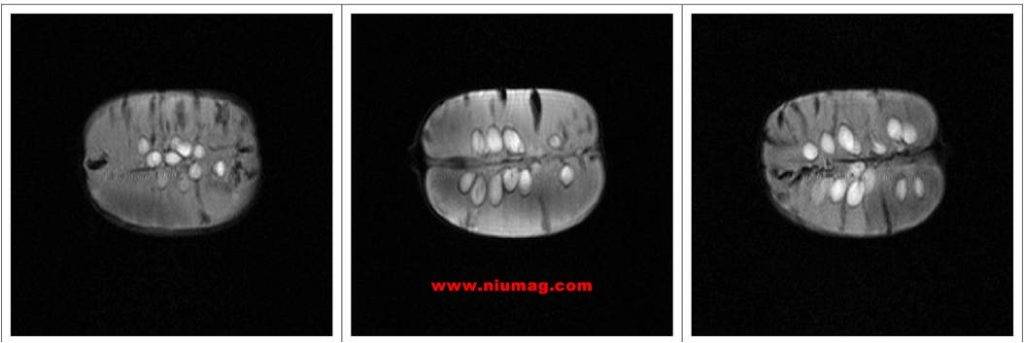

玉米核磁共振多層成像圖-橫斷位

玉米核磁共振多層成像圖-失狀位